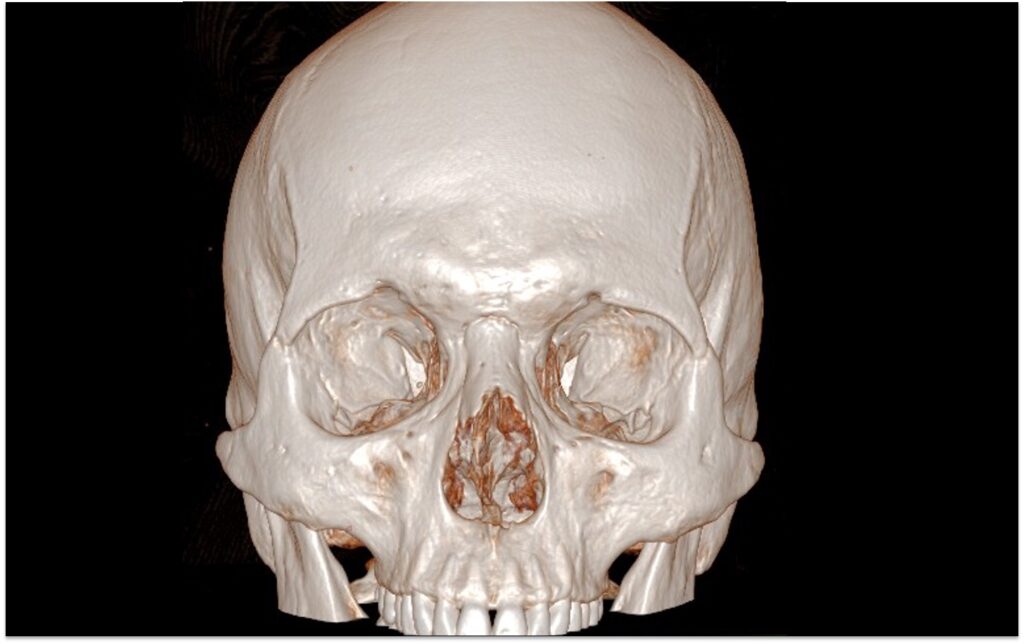

TAC del massiccio facciale

Che cos’è la TAC del massiccio facciale? La “TAC del massiccio facciale” si riferisce alla tomografia computerizzata (TC) del cranio che è specificamente mirata a